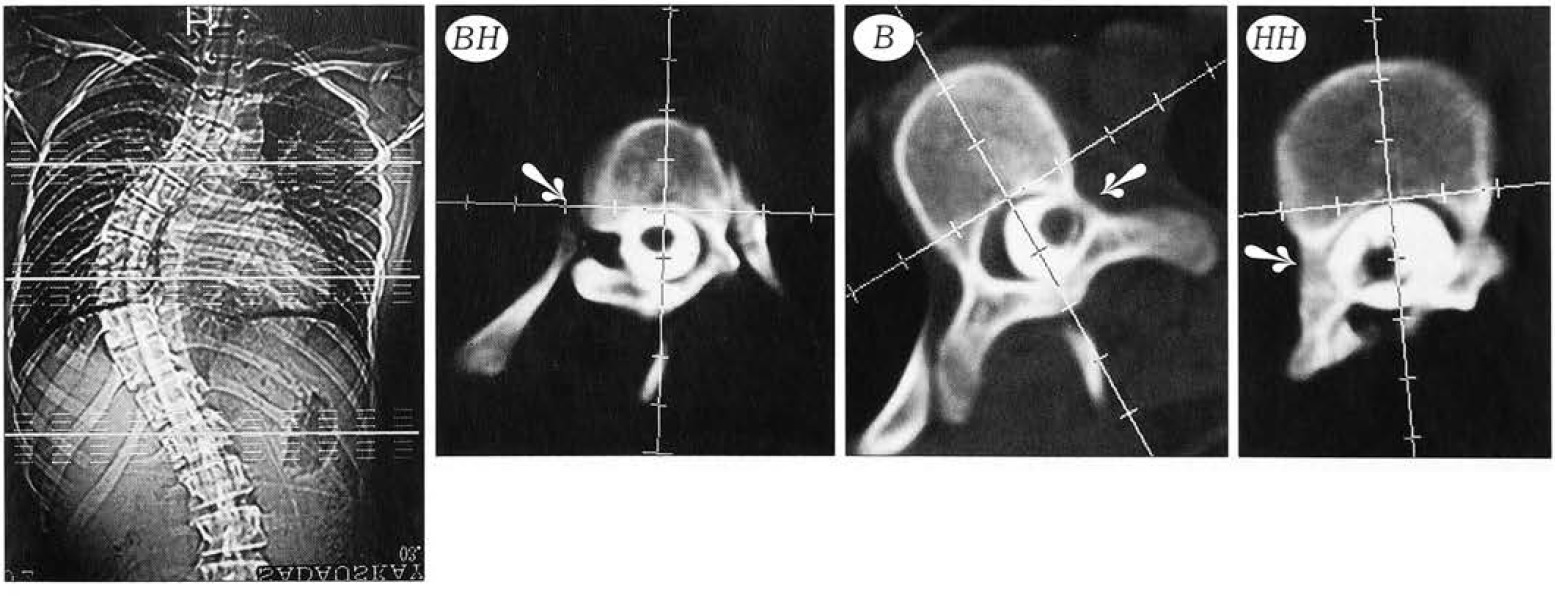

На вершине искривления отмечалась дислокация дурального мешка в сторону, противоположную выпуклости деформации. Спинной мозг и окружающие его оболочки располагались в деформированном позвоночном канале, стремясь занять минимальное по длине расстояние, и смещались в вогнутую сторону позвоночного канала. Вследствие этого происходило сужение или полное перекрытие субарахноидального пространства с вогнутой стороны и его компенсаторное расширение с противоположной стороны на соответствующую величину (рис. 12). При миелографии у всех пациентов по вогнутой стороне определялось частичное (на 60-70% при III—начальной IV степени сколиоза) или полное (при тяжелых деформациях) нарушение распространения контрастного вещества в субарахноидальном пространстве, а по выпуклой стороне — свободное его прохождение. Полного ликворного блока у пациентов исследуемой группы не обнаружено.

Мы не выявили жесткой корреляции между степенью сужения и деформации дурального мешка на уровне вершинного позвонка и величиной общего угла первичной дуги искривления, хотя определенная зависимость отмечена (рис. 13).

Рис. 13. Прохождение контрастного вещества на уровне вершинного позвонка при разной выраженности сколиотической деформации. а — больной с левосторонним грудным сколиозом, общий угол основной дуги деформации 128°, ротация вершинного позвонка 45°: по вогнутой стороне контрастное вещество практически не проходит; б — больная с правосторонним грудным сколиозом, общий угол основной дуги деформации 75°, ротация вершинного позвонка -19°: по вогнутой стороне контрастное вещество проходит в виде полосы, на выпуклой стороне субарахноидальное пространство значительно расширено.

На уровне нейтральных позвонков контрастное вещество проходило симметрично, однако если имелась некоторая ротация позвонка, то наблюдалась и асимметрия распространения контрастного вещества (рис. 14).

Рис. 14. Прохождение контрастного вещества на уровне нейтральных позвонков (ВН — верхний нейтральный, НН — нижний нейтральный, В — вершинный позвонок). Пояснения в тексте.

Таким образом, прослеживается следующая закономерность: чем выраженнее сколиотическая деформация, ротация вершинного позвонка и деформация позвоночного канала, тем значительнее асимметрия контрастируемого субарахноидального пространства, степень его сужения по вогнутой и расширения по выпуклой стороне деформации.